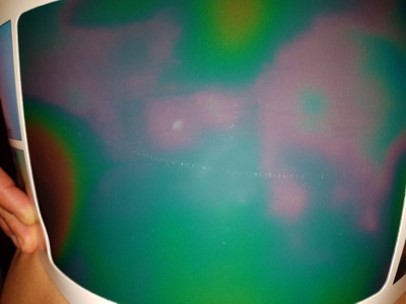

The color variation of black, red and blue was not statistically significant (figure 4). The variation to green went from 51% (20.25) pre-treatment to 62.25% (17.01) after treatment. This difference was statistically significant: p = 0.043.

Figure 4.Abdominal thermography (left flank). Range of colors displayed with the Thermoplate®30 (standard): blue, red and green.

A healthy thermographic picture, without cellulite, is homogeneous. The exact color of this situation of normality will be in the central area of the thermographic scale, but will depend on the plate used and the general conditions of the environment in which the measurements are taken. In this case, the homogeneous color seen in patients without cellulite was light green. The quantification of the color channels of the thermographic images showed some non statistically insignificant differences, but also significant and important color variations. The non-significant variation of the colors red and light blue is understandable, while these two colors represent intermediate categories in the thermographic scale. That is to say, that the decrease of a certain color (eg.: pink to green) can be compensated by the variation of another color (eg.: purple to pink). On the other hand, this study shows a significant variation towards the green and towards the homogeneity of the color. This, clinically, results in an improvement of cellulite and a reduction in edema, which is typically visualized as images of large, diffuse spots. These edematous spots and micro-nodules were visualized with different shades of red, purple and light blue.